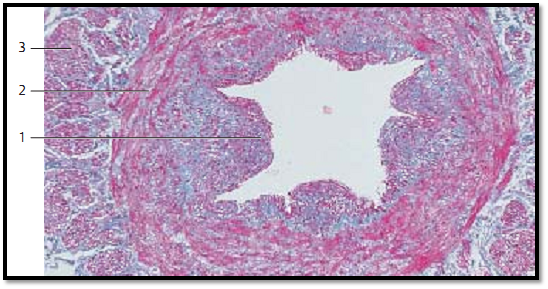

Several special structures, such as bulging or lip-shaped prominences 1 can be found in the arterial circulator y system. These occur in most instance close to branching points. There are also constricting arteries, which feature prominences of longitudinal muscle cells at the luminal side of their circular musculature. These muscular prominences look like cushions (muscular tunica intima cushions). The star-shaped lumen owes its form to muscular intima cushions of different sizes 1 . Toward the outside of the vessel, follow several layers of ring muscles 2 , which are covered by strong muscle fibers in longitudinal direction 3 . The artery in this figure is from a human spermatic cord.

1 Muscular intima cushion

2 Ring muscle layer

3 Layer of longitudinal muscles

Stain: azan; magnification: × 80